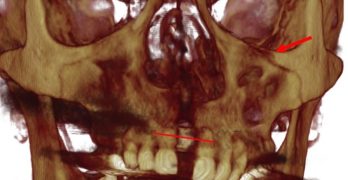

Para comenzar la semana traemos un artículo llamado Asymmetric mandibular arch distalization with third-molar … [Leer más...] acerca de Distalización asimétrica con extracción de terceros molares para la corrección no quirúrgica de la mordida abierta esqueletal clase III y desviación mandibular

Distalización asimétrica con extracción de terceros molares para la corrección no quirúrgica de la mordida abierta esqueletal clase III y desviación mandibular